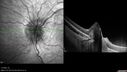

9 year old female She went for her annual eye examination, and they were concerned about the back of the eye. She has no visual obscurations and no headaches. She was found to have a HgB of 6.9 and anemia 12/10/21. She was iron deficient. She is taking iron. VA OD: Dsc20/80-2 PH20/25-2 NscJ1+2 VA OS: Dsc20/50 PH20/32 NscJ1+ IOP: TP: OD:14 OS:18

Optic Disc Drusen in a child (non Calcified)27 viewsFluorescein angiography shows no leakage00000